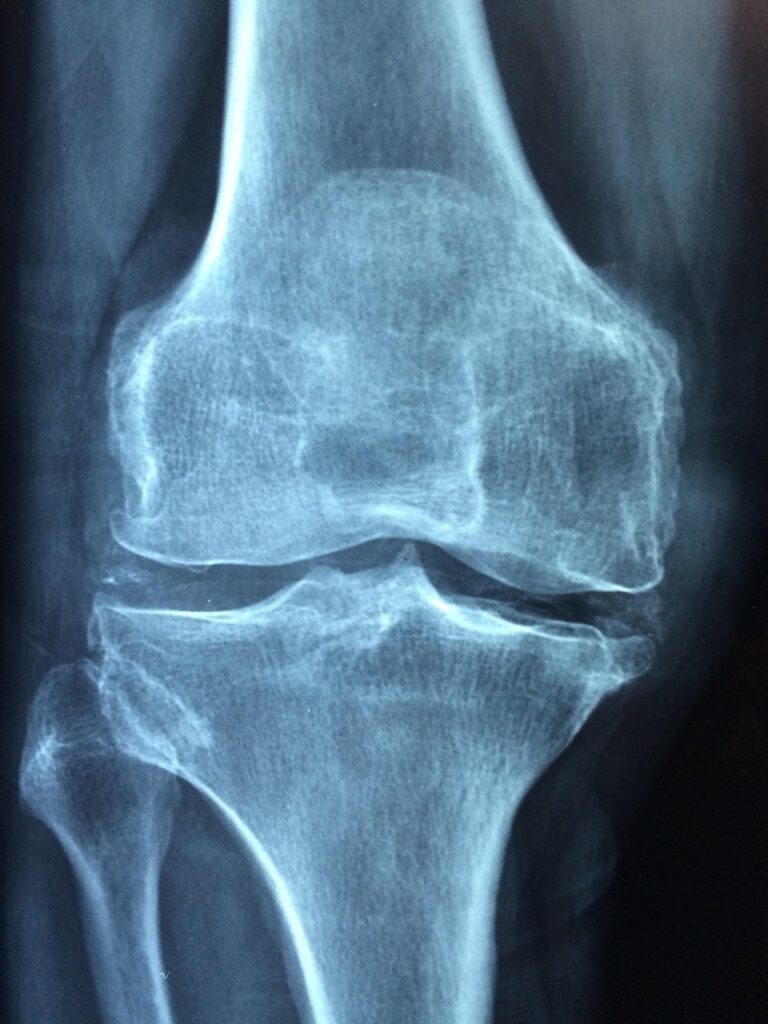

膝痛に悩むあなたには、再生医療という選択肢があります。再生医療は、身体の自然な治癒力を引き出し、膝の痛みを軽減する新しい治療法です。

再生医療には、幹細胞治療やPRP(血小板豊富血漿)療法などがあります。これらの治療法は、膝の関節の再生を促すことで、痛みの軽減や機能の改善を目指します。

膝痛の原因は多岐にわたりますが、加齢や運動不足、過剰な負荷が影響します。再生医療は、これらの原因に対してアプローチできる可能性があるため、注目されています。